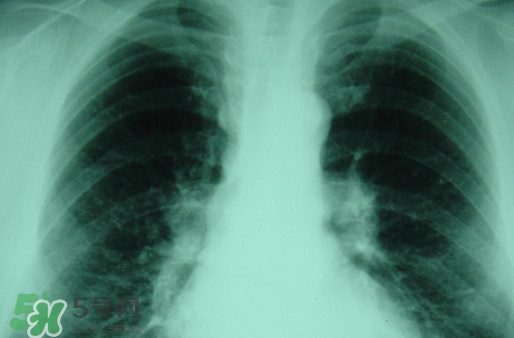

塵肺病多半是因?yàn)榉尾课牖覊m導(dǎo)致呼吸不順暢,引發(fā)細(xì)菌感染的病癥,而且隨著近年來塵肺病人得增多及死亡率,國家對(duì)此發(fā)布了相關(guān)政策。那么,塵肺病吃什么藥能清肺?塵肺病國家有什么政策?

很多人不知道,其實(shí)塵肺病分為無機(jī)塵肺和有機(jī)塵肺兩種?;颊哂捎谠谌粘5墓ぷ髦兄虚L期吸入生產(chǎn)性粉塵(灰塵),這些粉塵在肺內(nèi)滯留,從而引起的了塵肺病這種全身性疾病,很多人對(duì)此認(rèn)識(shí)并不清楚。

吸入無機(jī)粉塵所致的塵肺,稱為無機(jī)塵肺;吸入有機(jī)粉塵以后患病被稱為有機(jī)塵肺。對(duì)早期矽肺療效較好的藥物可以選擇克矽平,有阻止和延緩矽肺進(jìn)展的作用。同時(shí)也肯那個(gè)會(huì)出現(xiàn)發(fā)癢、硬塊,肌肉跳動(dòng)等不良反應(yīng)。